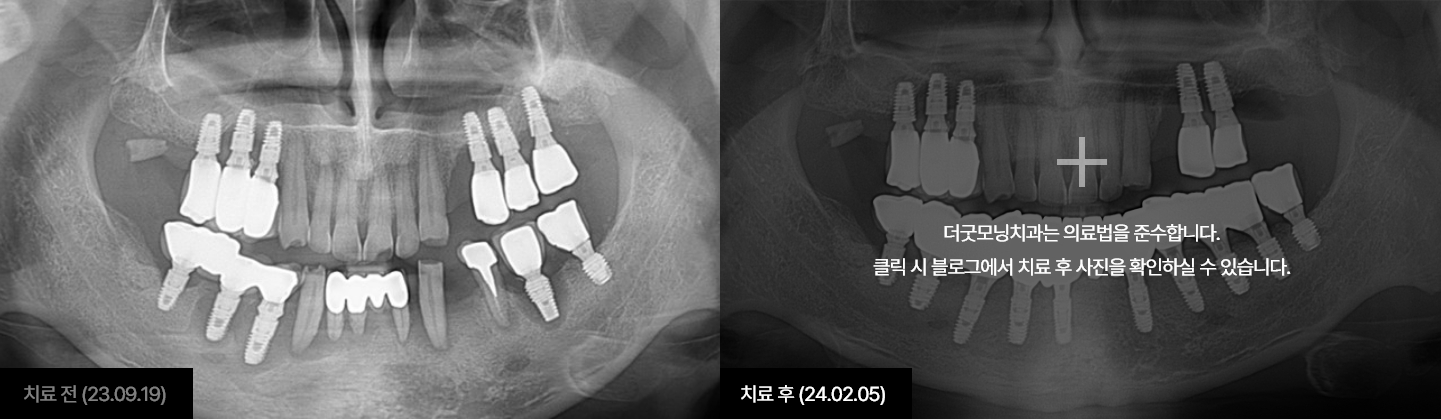

더굿모닝치과는 실제 수술 전, 3차원 3D-CT를 이용하여

정밀진단과 가상수술을 통해 임플란트를 식립할 위치, 방향, 깊이 등

환자 개인의 수술 조건을 사전에 파악하여

한 치의 오차 없이 정확하고 빠르게 완성합니다.